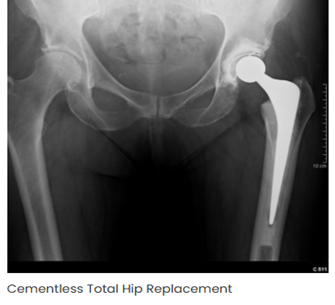

- Types of Hip Replacement Surgeries we offer

- Total Hip Replacement (THR) Unilateral & Bilateral

- Complex Revision Hip Surgery

- Robotic / Computer-Assisted Hip Replacement